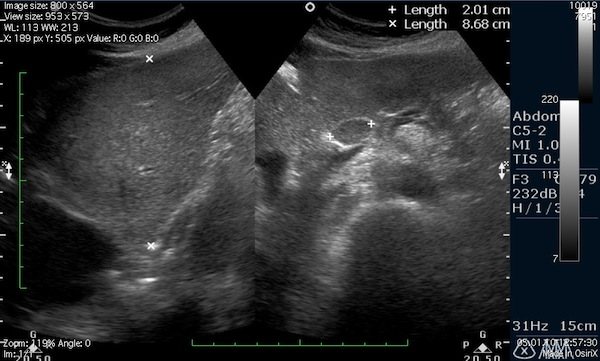

| Фото. Простые кисты поджелудочной железы на УЗИ. А, Б — Одиночные простые кисты в области тела (А) и шеи (Б) поджелудочной железы с тонкой гладкой стенкой и анэхогенным содержимым. В — Классические признаки хронического панкреатита: главный панкреатический проток расширен на фоне атрофии паренхимы, контур железы неровный с зазубринами, в паренхиме обызвествления и маленькие кисты. | |

| Фото. Мужчина с инсулинзависимым сахарным диабетом жалуется на потерю веса и боли в животе несколько месяцев. На УЗИ расширеный общий проток поджелудочной железы с неровной стенкой. При дальнейшем осмотре хорошо видно в протоке кальцификаты с тенью позади (В). | ||